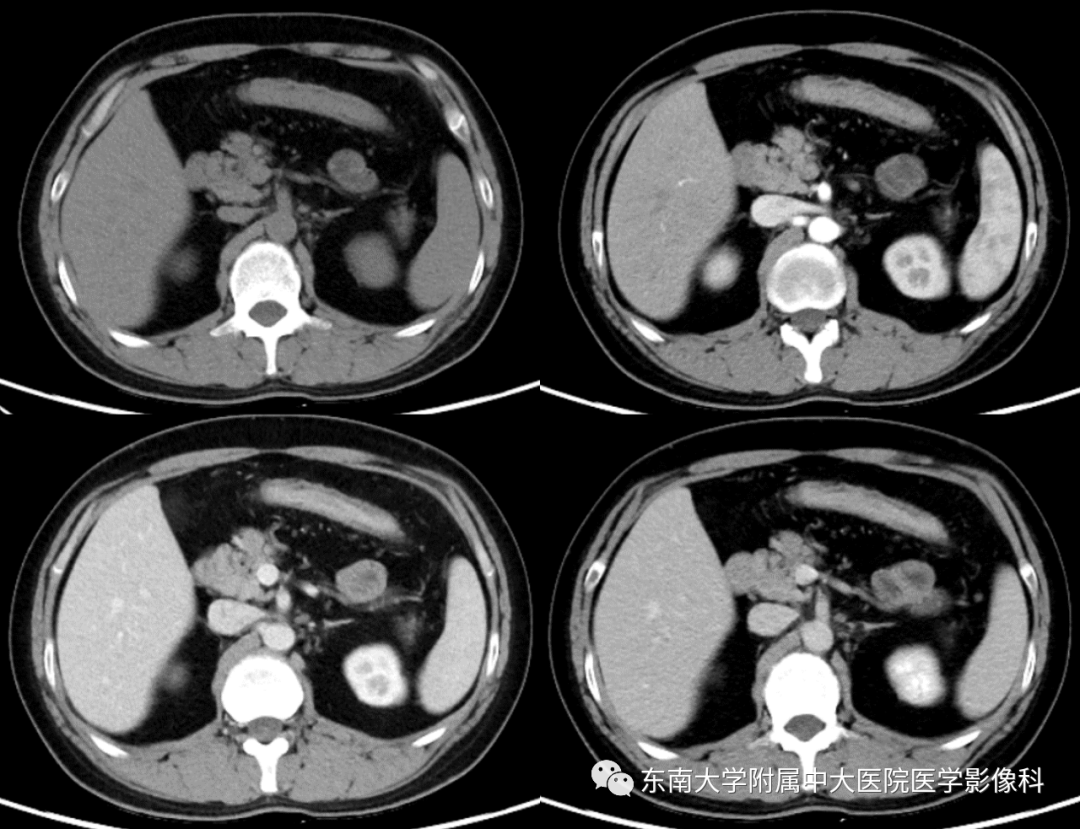

炎症性肠病的ct诊断影像天地

图片尺寸960x720

炎症性肠病的ctmri诊断影像天地